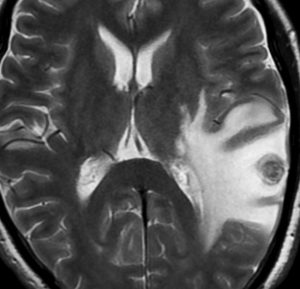

髄膜癌腫症(癌性髄膜炎)

leptomeningeal carcinomatosis, carcinomatous meningitis

脳と脊髄の表面にがん細胞が広範に広がって増殖します。MRIでは,矢印のように脳溝 sulciの中に癌の増殖が見られます。T1ガドリニウム増強で,脳溝や脳の表面が白い線のように描出されます,脳血管とは違うのでわかります。